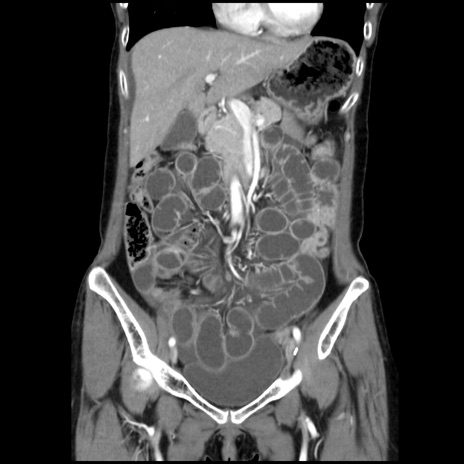

症例32(冠状断像)

【症例】40歳代 女性

【主訴】上腹部痛、嘔気・嘔吐

【現病歴】約9時間前頃から急に上腹部痛、嘔気、嘔吐が出現。改善しないため救急要請。

【既往歴】子宮頚癌(広汎子宮全摘術、放射線療法)、腸閉塞

【身体所見】腹部:平坦、軟、腸雑音亢進、上腹部を中心に腹部全体に圧痛あり。

【データ】WBC 8400、CRP 0.03